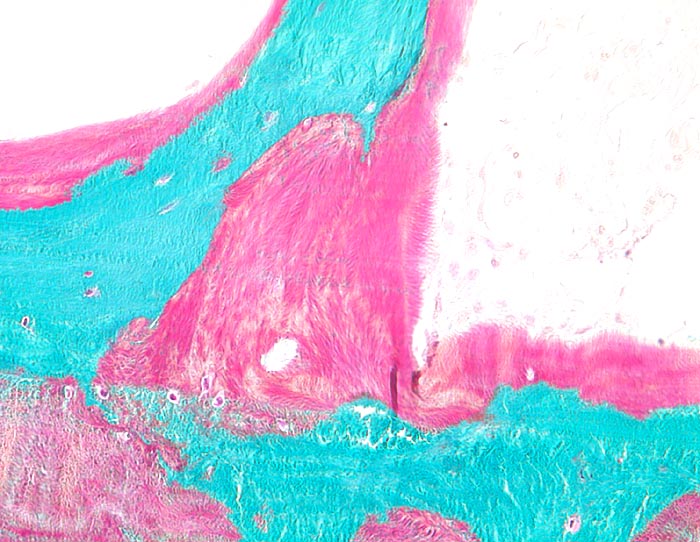

Osteoidose (Osteomalazie) und Osteoporose

Fasrige Struktur des roten unmineralisierten Osteoid.

35-jähriger Patient, bei welchem eine einheimische Sprue diagnostiziert wurde. Klinisch zeigte er Knochenschmerzen und eine diffuse Muskelschwäche. Im Labor fanden sich erniedrigte Werte für Vitamin-D, eine Hypophosphatämie und ein Hyperparathyreoidismus (erhöhte PTH-Werte). Durch die krankheitsbedingte Malabsorption kam es zur verminderten enteralen Aufnahme von Vitamin-D.

Histologie

160